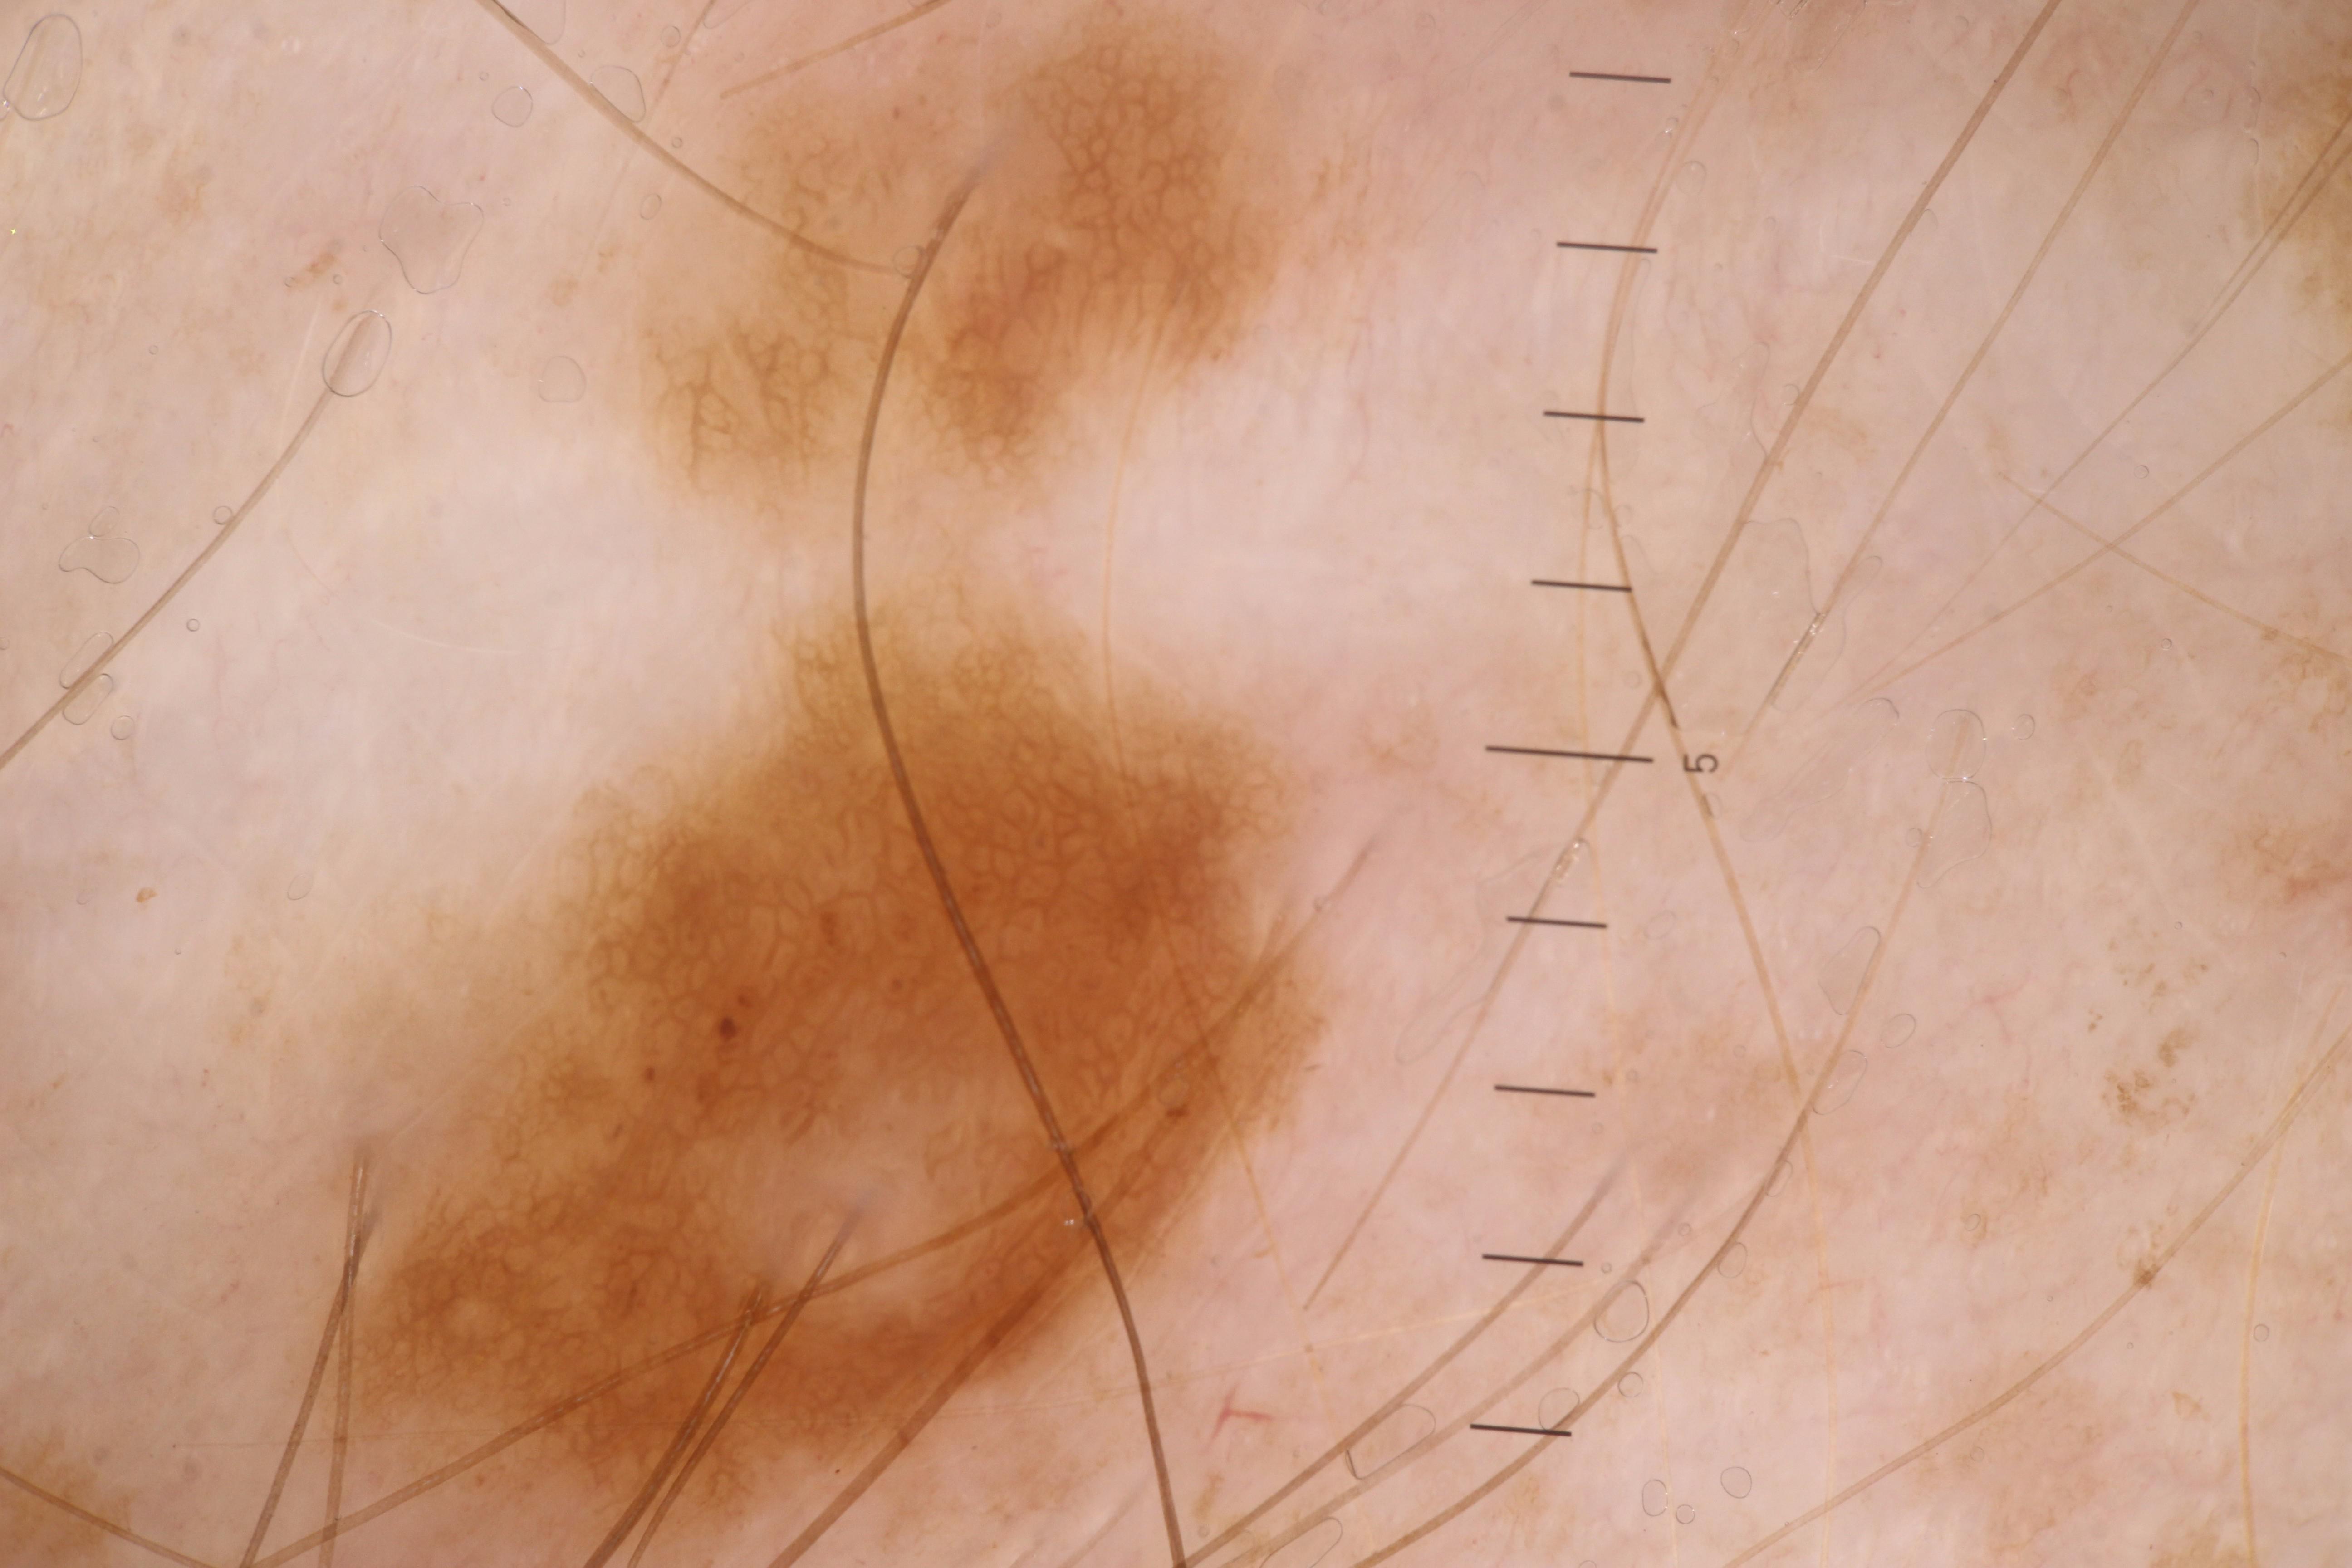

{

"age_approx": 50,

"anatom_site_general": "upper extremity",

"concomitant_biopsy": true,

"diagnosis_1": "Malignant",

"diagnosis_2": "Malignant melanocytic proliferations (Melanoma)",

"diagnosis_3": "Melanoma, NOS",

"diagnosis_confirm_type": "histopathology",

"fitzpatrick_skin_type": "I",

"image_type": "dermoscopic",

"lesion_id": "IL_6285436",

"melanocytic": true,

"patient_id": "IP_4612042",

"sex": "male"

}